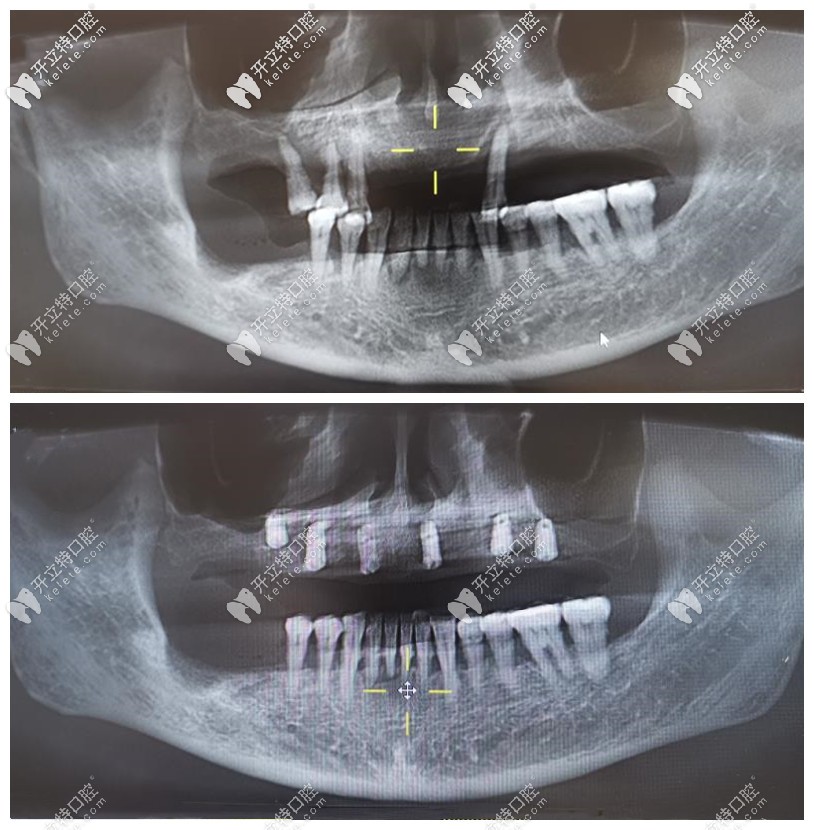

先曬下我骨性和牙性齙牙內(nèi)收6mm側(cè)面x光效果圖(不想發(fā)照片,黑歷史不想回顧)▼

我骨性和牙性齙牙內(nèi)收6mm側(cè)面x光效果圖